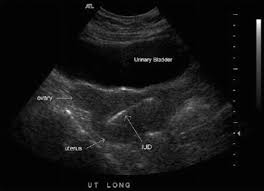

Us confirmed proper placement of the iud.

Intrauterine device (iud) removal note i have identified this patient to be (patient name). Us confirmed proper placement of the iud. Add modifier 51 to 58300 if you do a removal and insertion procedure code z30.430 for insertion only z30.432 for removal only z30.433 for removal and insertion of device to bill for the device mirena device j7298 to bill for the device under nexgen: Note that modifier 51 (multiple procedures) is added to the lesser procedure. How do you bill a depo provera shot? V25.02 z30.014 encounter for initial prescription of iud (not coded with the As for the e/m, it. The speculum was placed and the iud string visualized. I would appreciate any thoughts or advice. For laparoscopic, consider unlisted 49329. You would use procedure code 58562 (hysteroscopy, surgical; And, can we bill an e/m with it? The health care professional evaluates the uterus and the position of the strings attached to the iud.

Us confirmed proper placement of the iud. Would it be proper for me to use the 58562 code although the iud was not technically embedded. Subsequently, question is, how do i know if my insurance covers my iud? She presents today for the removal of her iud due to (desire for pregnancy/abnormal bleeding/pain/due for removal/other). Note that modifier 51 (multiple procedures) is added to the lesser procedure.